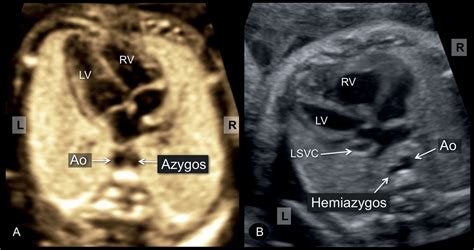

Persistent Left Superior Vena Cava - HKOG-INFO

Persistent left superior vena cava - HKOG-INFO hkog-info.com

subclavian artery aberrant vena arsa cava persistent trachea svc vessels hkog

Fetal heterotaxy and situs inversus. Persistent left superior vena cava. Heart anatomy flow blood circulatory